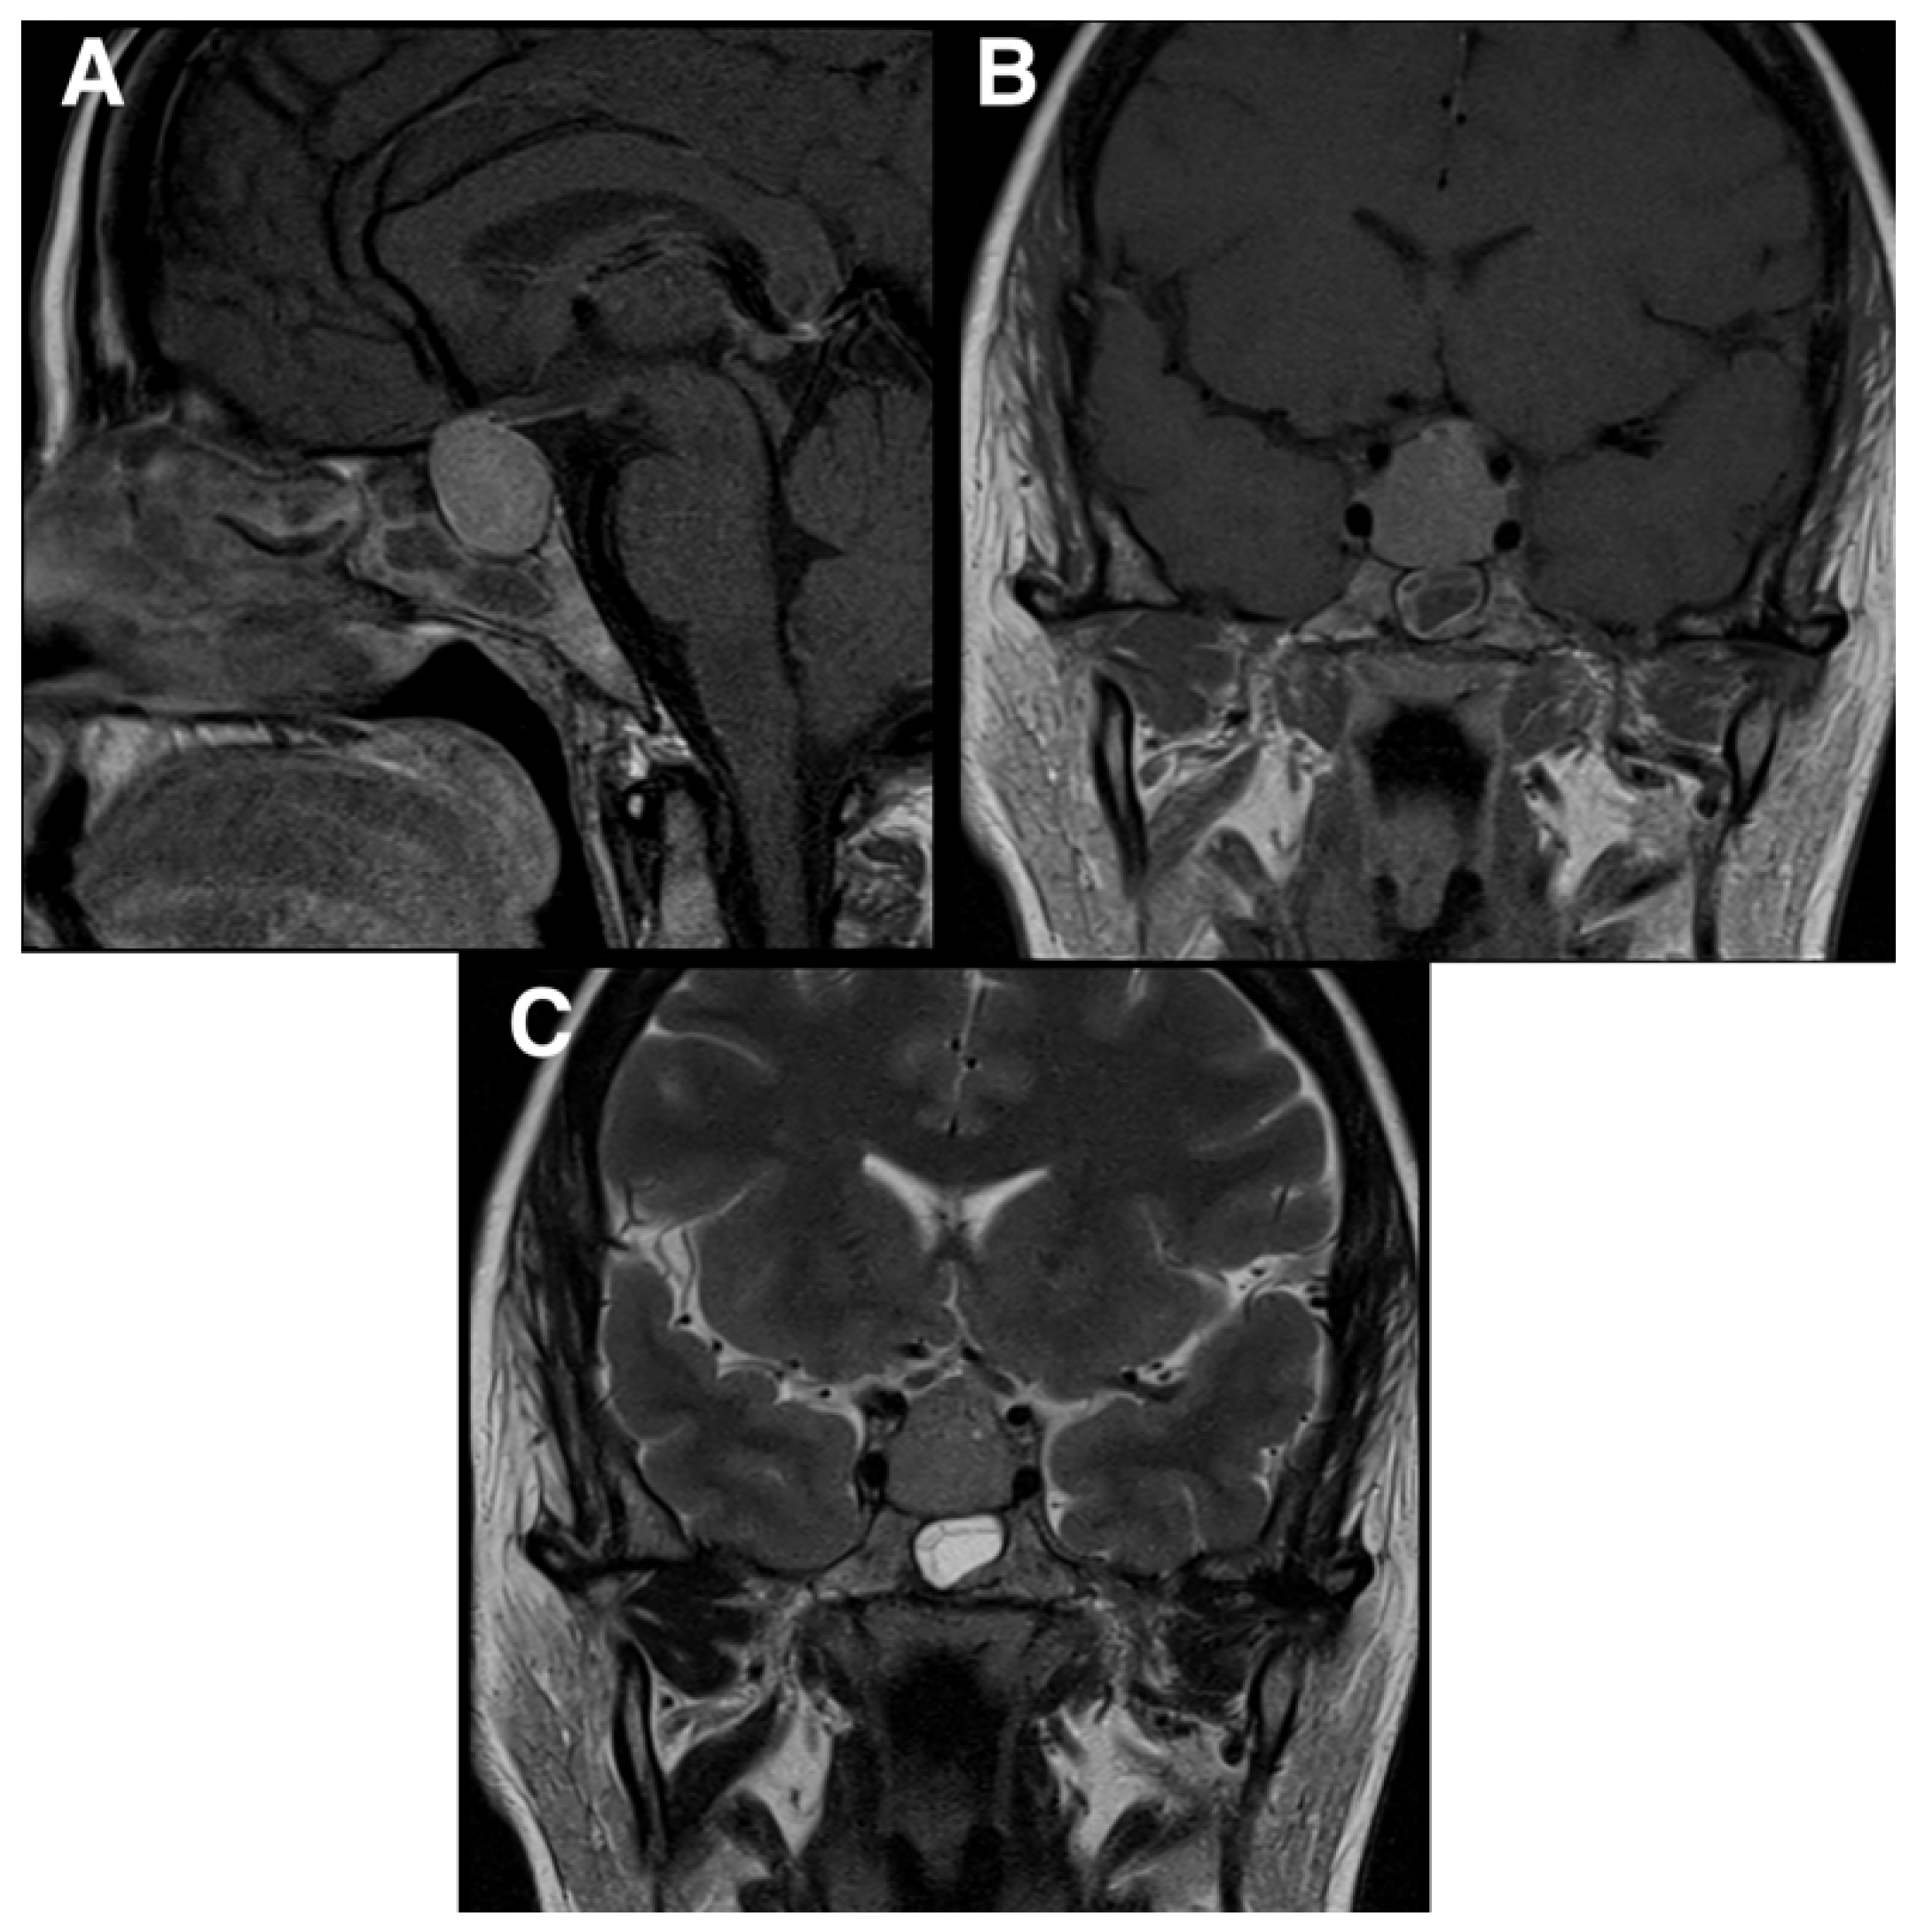

2. Case Presentation